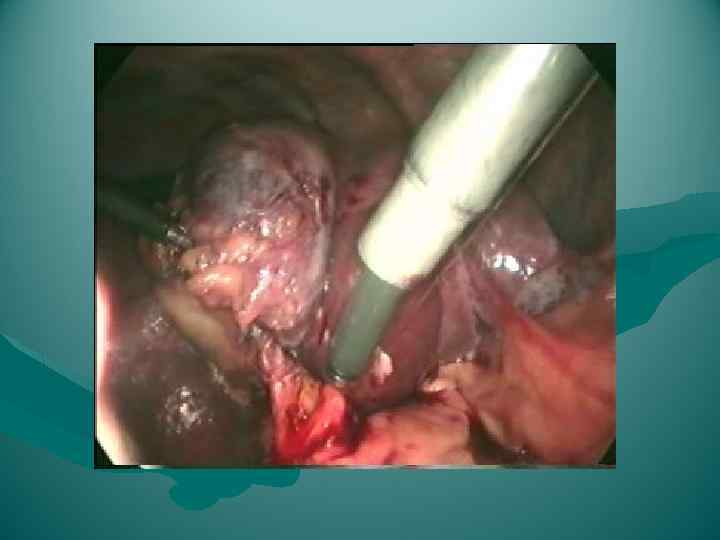

Мобилизация левой доли

Мобилизация левой доли

Мобилизация правой доли

Мобилизация правой доли

ПЕРЕВЯЗКА ОБРАЗОВАНИЙ В ВОРОТАХ ЛЕВОЙ ДОЛИ ПЕЧЕНИ

ПЕРЕВЯЗКА ОБРАЗОВАНИЙ В ВОРОТАХ ЛЕВОЙ ДОЛИ ПЕЧЕНИ

Раздавливание печени

Раздавливание печени

Резекция доли печени

Резекция доли печени

Перевязка левой печеночной вены.

Перевязка левой печеночной вены.